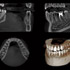

Höchste Bildqualität

X-ERA SMART verfügt über ein einzigartiges Patientenpositionierungssystem im 3D Bereich, das jede Bildverzerrung durch Patientenbewegung komplett ausschließt. Das Technologiekonzept erzeugt eine Bildqualität in extrem hoher Auflösung. Zwei verschiedene Aufnahmegrößen mit einer Voxel Größe von 80μm / 100 μm liefern in jeder Sichtfeldgröße (FoV) exzellente Ergebnisse für die weitere Diagnostik und Behandlung.

Nacholgend ein paar phänomenale Bilder & Werte,

die nicht nur einem Fachmann die Sprache verschlagen: